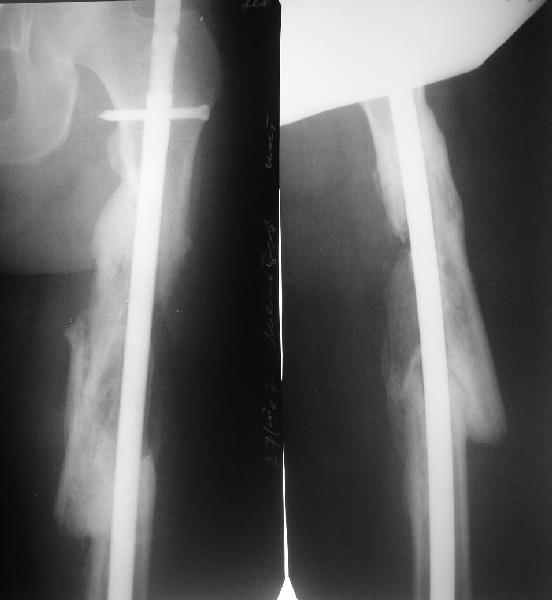

Мы бы не стали открывать, такие переломы срастаются, хотя бы и с краевым дефектом. То есть если удалять стержень потом, то сильно попозже обычного. В приложении пример. Сразу после операции и через 11 мес. Понятное дело, пациент к тому времени давно и не хромал, и функция колена была полная.

Уважаемые коллеги! От имени Алексея Смирнова всем спасибо за обсуждение. Больной прооперирован. Снимки в приложении.